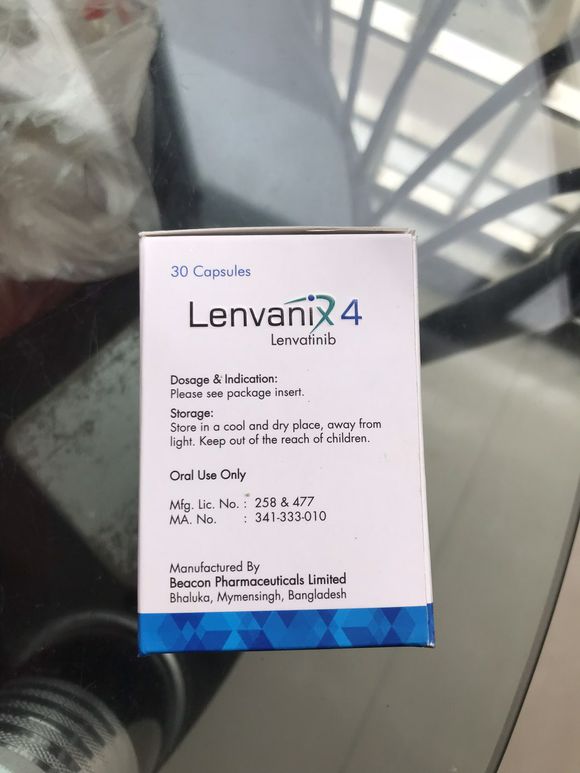

极光 02019-04-18 患者家属上周六父亲检查出原发性肝癌晚期,在北京301医院做完一系列检查,用着PT1,伦伐替尼,医生说最多在维持一到三年,但是家里...